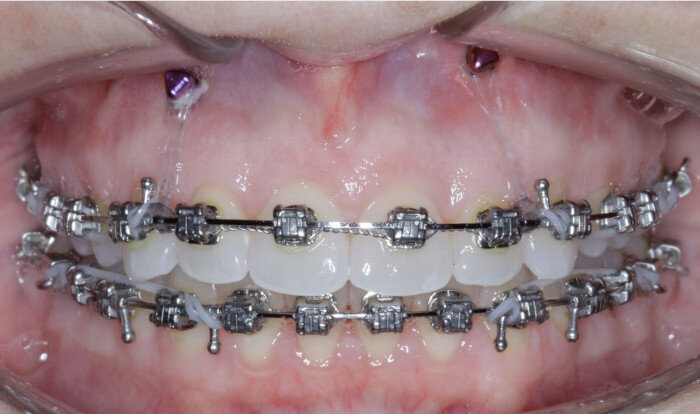

TADs are placed at the second visit with a 14 × 25 mm copper (Cu) and nickel–titanium (NiTi) wire and are tied from the anchor to the wire with an elastic thread (surgical thread; Fig. 6). Once the patient has progressed to larger Cu–NiTi wires and stainless steel, the TADs are tied to the wire using a power chain looped to the wire, or NiTi closing springs, depending on the thickness of the tissue (Figs. 7 & 8).

Once the intrusion has been completed, the TADs are tied to the wire and vertical elastics are used to close the bite without relapse of the intrusion. If buccal crown tip is seen, owing to the movement created by the intrusion, a power chain torquing sling is used to encourage lingual crown tipping and to prevent flaring of the incisors (Fig. 9). Once the case has been completed, the appliance is removed and a gingivectomy is performed to idealise the tissue shape and the final contours are made to the hard tissue (Figs. 10–12, end of treatment).